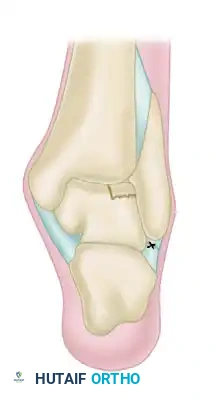

Grade III (Severe Exostosis): A secondary spur is noted on the dorsum of the talus, often accompanied by fragmentation of the osteophytes (kissing lesions).

* Introduce a 3.0-mm or 4.0-mm arthroscopic burr.

* Systematically resect the tibial osteophytes back to the level of the normal native cartilage.

* The Davis Modification: To prevent inadvertent damage to the intact articular cartilage, Davis described creating a "trough" with the burr approximately 1 mm proximal and parallel to the anterior edge of the tibia. This trough is taken down to subchondral bone. An arthroscopic bone-biter or osteotome is then used to fracture and remove the isolated bony spur. This provides superior control compared to attempting to gain purchase on the hard, smooth surface of the spur with a shaver.

* Smooth the resected tibial surface with the full-radius resector.

* Repeat the identical procedure for any kissing lesions on the superior neck of the talus.